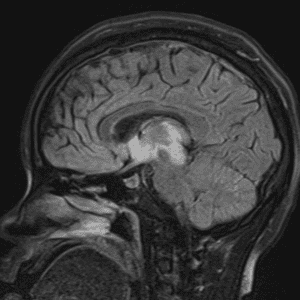

Case #15

Tectal glioma